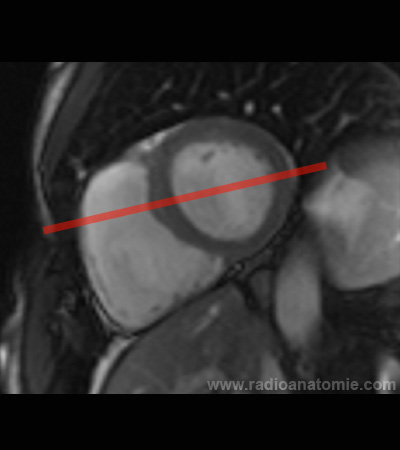

Radioanatomie et plans de coupe en IRM cardiaque

Coupe petit axe

Plan 4 cavités

Plan 2 cavités

Plan chambre de chasse du ventricule gauche (LVOT)

Pilier de la valve mitrale